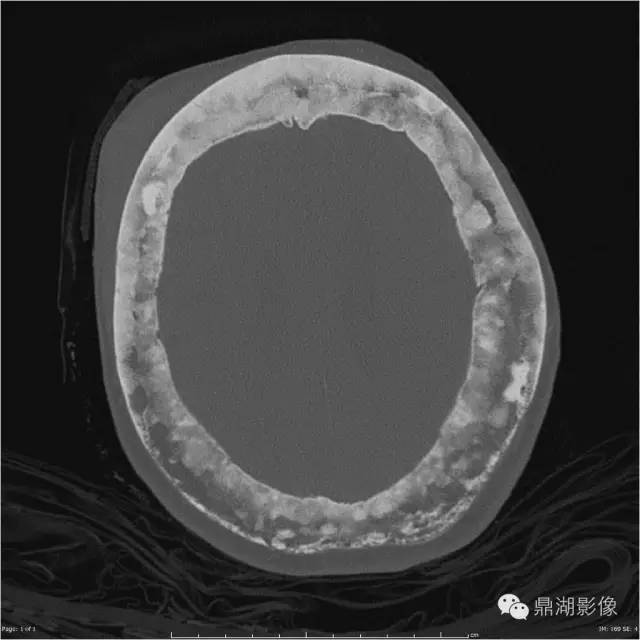

随着时间的推移病变可发生变化,治疗后溶骨区域可逆转。则某些特殊区域佩吉特骨病可出现特征性的改变,如脊柱受累时可出现“窗户框”现象,骨盆受累时可出现髋臼内陷及骶髂关节关节强直,颅骨受累时可出现骨质疏松性局限性钙质沉着和颅底凹陷症。